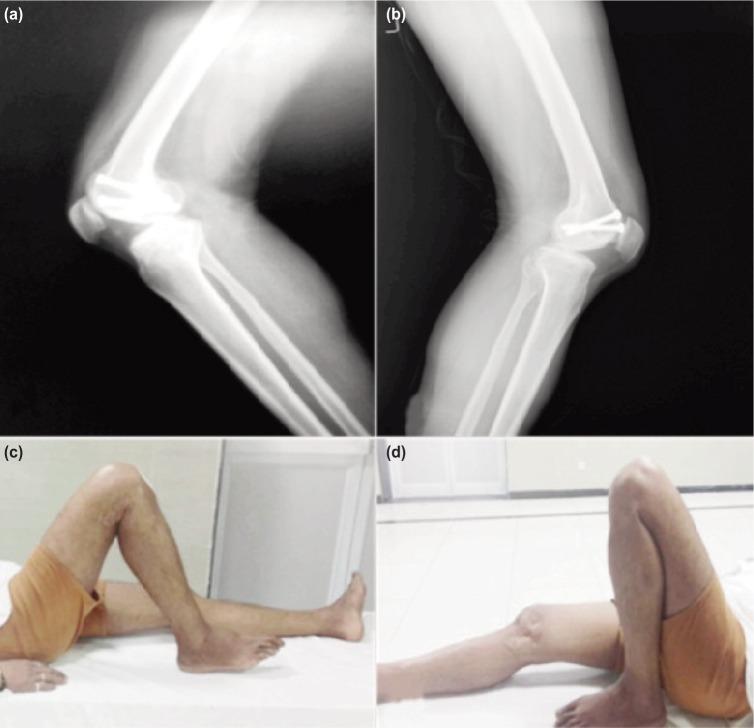

Isolated Hoffa fracture is an infrequent injury and little research has been done on this subject. The purpose of this study was to evaluate the functional outcome and complications of surgically managed Hoffa fractures with cannulated cancellous screw. Between 2011 and 2014, eight isolated Hoffa fractures in seven adult patients with mean age 39.8±11.9 years (range 25-60 years) were managed with cannulated cancellous screw of 6.5mm diameter applied in anterior to posterior direction using swashbuckler and medial parapatellar approach for lateral and medial Hoffa fractures respectively. All patients were evaluated using knee evaluation score after two years or longer. Mean follow up was 28±3.8 months (range 24-36 months). All fractures in the eight patients healed clinicoradiologically by the 16th week with excellent result in 87.5% cases and good in 12.5% cases. By the end of union, the range of motion (ROM) of the knee was 0° to 110° except in two patients. One patient had ROM 10°-100° and other had 15°-90°. Mean knee evaluation score was 87.5±10.4. There was no incidence of non-union, infection or avascular changes in the patients or loss of reduction till final follow up. Open reduction and fixation with two 6.5 mm cannulated cancellous screws with early mobilization yielded good functional outcome in isolated Hoffa fractures.

孤立性Hoffa骨折是一种罕见的损伤,对此主题的研究较少。本研究的目的是评估采用空心松质骨螺钉手术治疗Hoffa骨折的功能结果和并发症。2011年至2014年期间,对7例成年患者(平均年龄39.8±11.9岁,范围25 - 60岁)的8例孤立性Hoffa骨折进行了治疗,分别采用“海盗”入路和内侧髌旁入路,对外侧和内侧Hoffa骨折从前向后方向应用直径6.5mm的空心松质骨螺钉。所有患者在两年或更长时间后使用膝关节评估评分进行评估。平均随访时间为28±3.8个月(范围24 - 36个月)。8例患者的所有骨折在第16周时临床影像学愈合,87.5%的病例结果优秀,12.5%的病例结果良好。到骨折愈合结束时,除2例患者外,膝关节的活动范围(ROM)为0°至110°。1例患者的ROM为10° - 100°,另1例为15° - 90°。平均膝关节评估评分为87.5±10.4。直至最终随访,患者未发生骨不连、感染或缺血性改变,也没有复位丢失的情况。采用两枚6.5mm空心松质骨螺钉切开复位内固定并早期活动,在孤立性Hoffa骨折中取得了良好的功能结果。